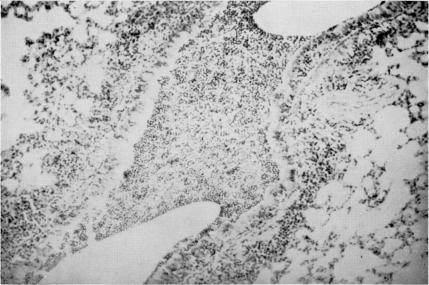

An experimental model for human mycoplasma disease.

Yale J Biol Med. 1968 Apr-Jun;40(5-6):436-43.